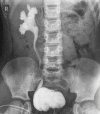

Figure 3

Five-year-old girl with unilateral grade 4 vesicouretric reflux on voiding cystourethrogram. Image courtesy of Dr Aditya Shetty, Radiopaedia.org, rID: 2722.